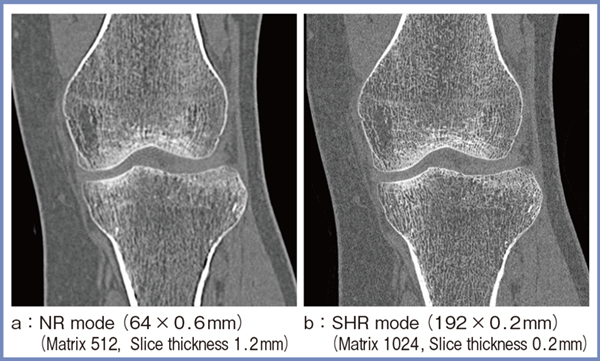

図1は膝関節の画像であるが,PCD-CTの通常の画像(NRモード,512マトリクス,スライス厚1.2mm:a)と比較して,SHRモード(b)では骨梁構造がきわめて明瞭に描出されており,空間分解能が高いことが確認できる。図2は肺の冠状断像の一部を拡大しているが,SHRモード(b)では微細な胸膜下の血管まで明瞭に描出されている。

図1 膝関節におけるPCD-CTのNRモードとSHRモードの空間分解能の比較